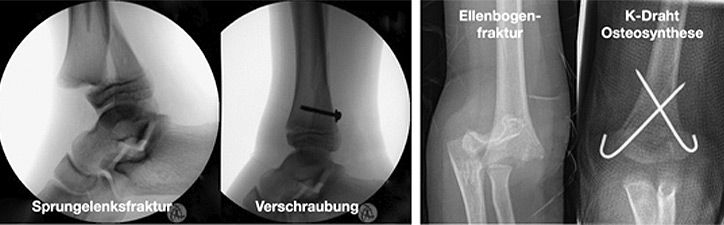

Einige Frakturen müssen auf Grund ihrer Achsabweichung operiert werden. In einer Narkose wird die Fraktur eingerichtet und ggf. mit Metall stabilisiert. Dazu stehen eine Reihe von Methoden (Osteosynthesen) zur Verfügung, die speziell für Kinder entwickelt wurden, um Wachstumsfugen zu schonen und nicht zu verletzen: Die ESIN (elastisch stabile intramedulläre Nagelung) hat sich als minimal invasives Standardverfahren zur Stabilisierung von Schaftfrakturen der großen Röhrenknochen (Unterarm, Oberarm, Unterschenkel, Oberschenkel) etabliert. Die Implantate können über winzige Schnitte eingebracht werden, eine gipsfreie Nachbehandlung ist ein weiterer entscheidender Vorteil.

Kirschner-Draht-Osteosynthese

Andere Verfahren der operativen Frakturversorgung im Kindesalter sind die Kirschner-Draht-Osteosynthese, die Verschraubung, der Fixateur und die Plattenosteosynthese. Metallentfernungen werden ambulant durchgeführt, Nachuntersuchungen zum Ausschluss etwaiger Wachstumsstörungen erfolgen in unserer Frakturensprechstunde.